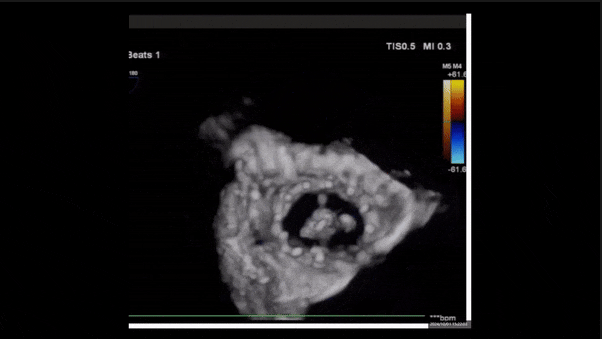

術(shù)后三維超聲

術(shù)后即刻經(jīng)食道超聲可見(jiàn),三尖瓣假體瓣膜位置合適,牛心包瓣葉運(yùn)動(dòng)狀態(tài)良好,開(kāi)閉正常,瓣周及瓣葉對(duì)合緣處未見(jiàn)明顯返流,心電圖及心包狀態(tài)較術(shù)前無(wú)明顯變化。

瓣膜釋放